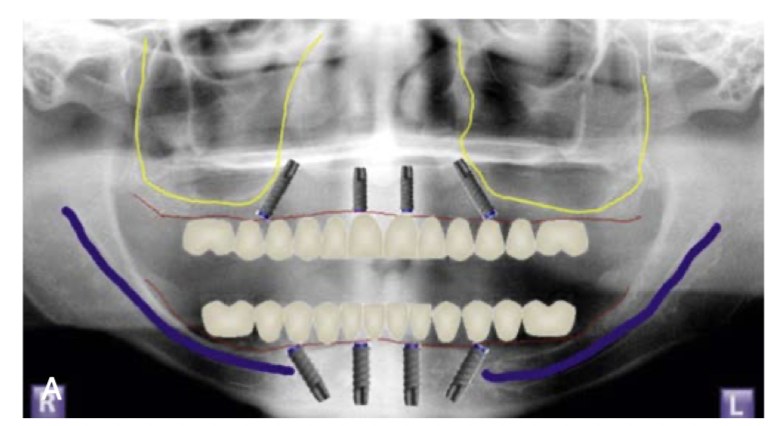

잇몸뼈가 안좋아도 가능해요

대부분 앞쪽에는 뼈가 있어서

틀니 오래 끼신 분도

이렇게 기울여서 심으면 가능한 경우가 많아요

더군다나 디지털 가이드를 이용해서

뼈가 얇은 경우에도 정확하게 심을 수 있어요